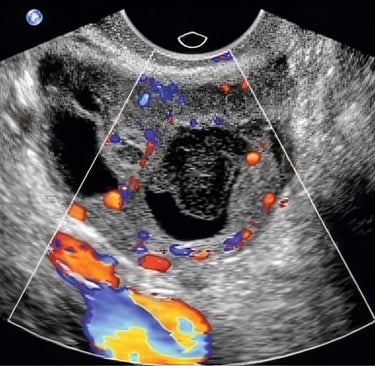

Hands-on practice emphasizes complete, systematic exams of the uterus, ovaries, adnexa, and Doppler assessment where indicated — each with faculty coaching on image optimization and interpretation. Brief reflective discussions bridge anatomy, physiology, and normal vs expected pathological findings.